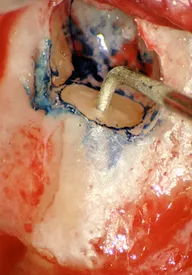

Endodonzia: risoluzione di perforazione

Nel caso clinico qui riportato, l'obiettivo è quello di focalizzare praticamente  la differenza tra un'odontoiatria di qualità rispetto ad un'odontoiatria che non può nemmeno essere considerata tale. La prima immagine clinica, eseguita grazie ad una foto in microscopia, mostra come un clinico poco esperto possa creare danni quali: una perforazione del pavimento della camera pulpare, un'errato […]